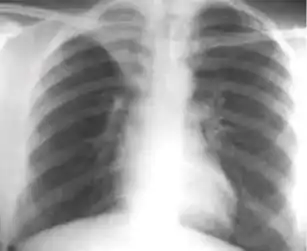

These are films that are completely normal, with no identifiable cardiothoracic or musculoskeletal abnormality.